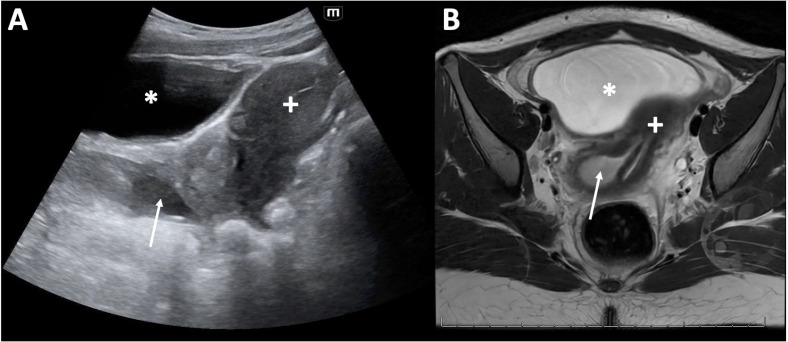

An 11-year-old postmenarchal female presented to the pediatric emergency department (ED) with 2 days of periumbilical and right lower abdominal pain. Radiology-performed ultrasound (RADUS) did not visualize the appendix, and there was a plan for surgical consultation to decide between serial abdominal exams versus computed tomography (CT) scan. While awaiting consultation and to help further narrow the differential diagnosis, the emergency provider performed a point of care ultrasound (POCUS) of the urinary tract. This revealed several anomalies including a solitary left kidney with hydronephrosis, and a well-circumscribed, fluid-filled structure with mixed echogenicity posterior to the bladder and inferior to the uterus. Given these findings on POCUS, further imaging was pursued, including a RADUS of the pelvis followed by a magnetic resonance imaging (MRI) of the abdomen. Further imaging ultimately diagnosed a bicornuate uterus, septate vagina with hematocolpos and solitary left kidney consistent with Obstructed Hemivagina and Ipsilateral Renal Anomaly (OHVIRA) syndrome. This case is an illustration of how POCUS is an invaluable tool to narrow the differential diagnosis and guide advanced imaging or consultation for both common and rare causes of pediatric abdominal pain.